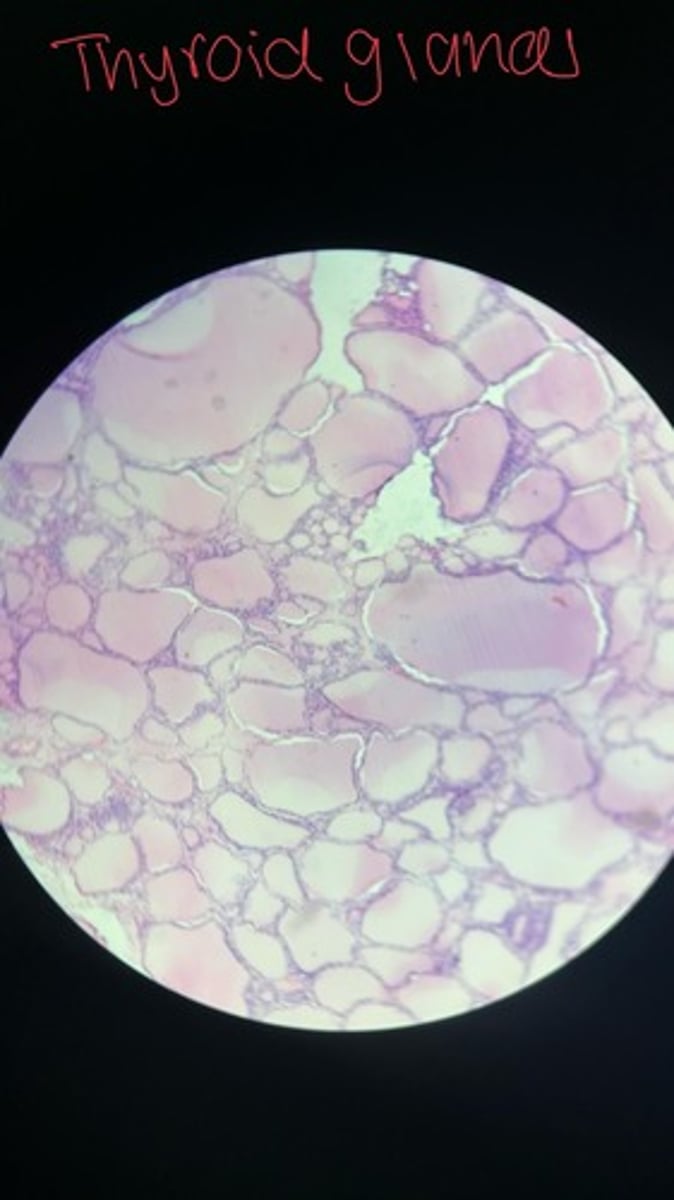

Thyroid gland HE

Thyroid gland HE

Thyroid gland HE

Thyroid HE

Thyroid HE